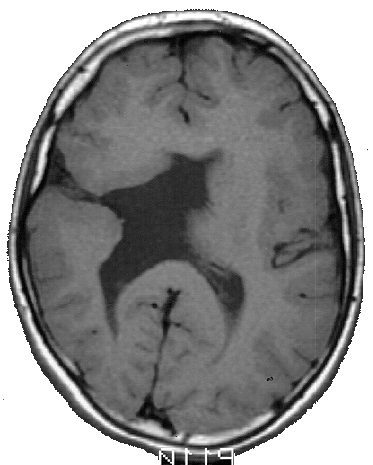

As crianças ARM e KTG são portadoras de lesões cerebrais denominadas Esquizencefalia (Fig. 5 e 6), que são decorrentes de distúrbios no processo embriogênico, que ocorrem no primeiro trimestre da gravidez. As lesões no indivíduo ARM se localizam no lobo frontal esquerdo e incluem também a ausência do septo pelúcido. Já a criança KTG tem as lesões localizadas no lobo parietal direito e também mostra sinais de comprometimento do hipocampo direito.

As lesões do indivíduo WA são do tipo Leucomalácia Multicística e se localizam principalmente no lobo parietal esquerdo. As lesões decorreram de problemas anóxicos perinatais, causados por problemas que a mãe experimentou alguns dias antes do parto. WA e ARM são canhotos e hemiplégicos à direita, e apresentaram atraso no desenvolvimento psicomotor. KTG é destra e tem hemiplegia à esquerda, apresentou também, atraso do desenvolvimento psicomotor.

Os MAREs de todos os indivíduos mostram uma atividade cerebral coerente com a lesão encontrada nas correspondentes MRIs. Assim, por exemplo, ARM tem uma lesão frontal esquerda na MRI, que está associada á um silêncio funcional nas derivações frontais esquerda nos seus MAREs (Fig. 5). Já o indivíduo WA tem uma lesão que se localiza predominantemente no lobo parietal esquerdo, que está associada a uma ausência de atividade nas derivações C3 e P3 nos seus MAREs mostrados na fig. 5. Finalmente, a lesão de KTG se localiza principalmente no lobo parietal direito, que se reflete nos correspondentes MAREs, por uma diminuição da ativação, principalmente, nas derivações P4 e T6.

Os MAREs associados ao processamento verbal no indivíduo ARM mostra uma ativação intensa nas derivações frontotemporais direitas, tanto no início como no final da apresentação da charada. Na fase inicial da apresentação do som, ocorre ativação nas derivações FZ e CZ.

Um padrão semelhante de ativação cerebral é observado também no indivíduo WA. Outra vez, o processamento do som verbal está associado a uma ativação das derivações frontoparietais direitas. Entretanto, observa-se também uma ativação em algumas derivações frontais esquerda. O fato marcante é a aparente redução da atividade nas regiões temporoparietais esquerdas.

A criança ARM tem uma lesão que compromete extensamente seu lobo frontal esquerdo, mostrando uma hemiplegia à direita e dificuldades de fonação. Sua lesão afeta também o fascículo arcuado, de modo que as áreas temporais esquerdas estão isoladas do pouco córtex frontal esquerdo que restou nesse indivíduo.

Corroborando esses achados, os MAREs apresentados na fig. 5, mostra uma boa ativação de áreas frontotemporais no hemisfério direito, quando do processamento da informação verbal no jogo de charadas. Parece, portanto, que a capacidade lingüística dessa criança é suportada pela ação do hemisfério não dominante. Aceita essa premissa, os MAREs mostrados na fig. 5 para esse indivíduo, demonstram claramente um alocação da função verbal no hemisfério direito; isto é, mostram um caso típico de plasticidade neural induzida por uma lesão congênita. Outros autores, por exemplo Graviline et al., 1998; reportam o sucesso de realocação de funções com a precocidade da lesão.

As lesões de WA comprometem fundamentalmente o lobo parietal e parte do lobo frontal esquerdos. Mais uma vez, o fascículo arcuado parece estar lesado. Outra vez, tem-se o isolamento entre o lobo temporal e as áreas frontais no hemisfério esquerdo. WA é uma criança que tem uma hemiplegia direita e dificuldades articulatórias. Entretanto, é também capaz de uma boa compreensão da linguagem falada, comprovada pelo seu bom rendimentos nos jogos de ordenação, memorização, interpretação e reconstrução. Um fato marcante em sua linguagem é a ausência do uso das palavras funcionais: artigos, preposições, etc. Esse fato está de acordo com o comprometimento córtex frontal esquerdo observado neste indivíduo (pe, Pinker, 1995; Rocha, 1999).

Os MAREs apresentados na fig. 5 para o indivíduo WA, mostram claramente uma redução da atividade nas derivações temporoparietais esquerda, compatível com a lesão estrutural observada na MRI. Uma vez mais, há um isolamento do lobo temporal em relação ao frontal, no hemisfério esquerdo. Outra vez, observa-se uma compensação desse isolamento, por um aumento do envolvimento do hemisfério direito no processamento da informação verbal.